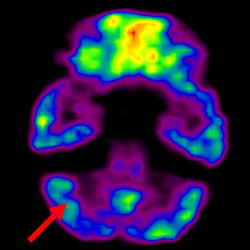

細胞治療前 PET CT 掃描顯示神經(jīng)組織中的藍/黑色區(qū)域,表明腦癱引起的大腦損傷。

腦癱細胞療法, 腦癱治療

細胞治療后,藍色和黑色區(qū)域減少,并且看到更活躍的區(qū)域。這表明損傷減少并改善了大腦功能。

這證明細胞療法是治療腦癱兒童安全有效的方法。細胞療法可以更新大腦損傷的核心,并且可以通過 PET CT 掃描來監(jiān)測大腦的改善情況。這些細胞療法與標準治療一起促進腦癱兒童的生長和改善。